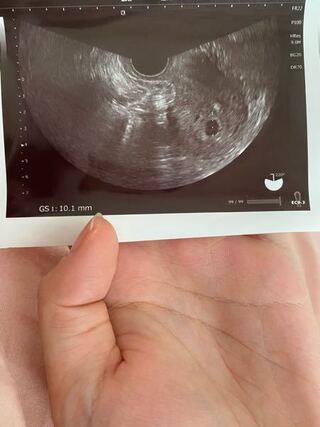

𝗽𝗶𝗽𝗶 𝟮𝟲𝘄 胎芽見えない 枯死卵かもって悩んでる方がいるかもなのでまとめておこう 4w0d 胎嚢 1 2mm程度 5w0d 胎嚢 12 4mm 卵黄嚢確認 6w0d 胎嚢 21 6mm 胎芽 卵黄嚢見えず 7w0d 胎芽 11 2mm 心拍確認 6w0dに中身